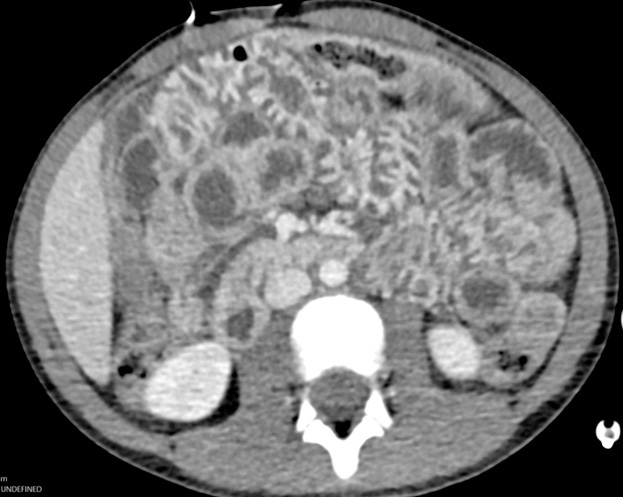

Patients younger than 4 years of age, those in a motor vehicle collision, and those with a positive FAST exam have been shown to be correlated with a higher severity of abdominal injury. The FAST exam in children has a sensitivity of 70%, but this increases when physical exam findings are considered as well.51 Laboratory findings frequently are used to determine the need for imaging as well and are incorporated into some prediction rules, such as the one developed by Streck et al, which was discussed earlier. Abnormal alanine aminotransferase (ALT), aspartate aminotransferase (AST), amylase, and lipase all have been demonstrated to have some utility in predicting solid organ abdominal injury. However, each of these tests has a low sensitivity and specificity. As such, laboratory values should not be used in isolation, but in conjunction with physical exam and FAST findings.52 See Figure 5 for an example of a liver laceration.

Figure 5. Liver Lacerations |

![]() |

Axial images from computed tomography with intravenous contrast show small lacerations in segments III and IVb of the liver, extending from about 2 cm from either side of the falciform ligament; AAST grade 2. Source: Courtesy of Mark Warren, DO, Dayton Children’s Hospital, Department of Radiology |